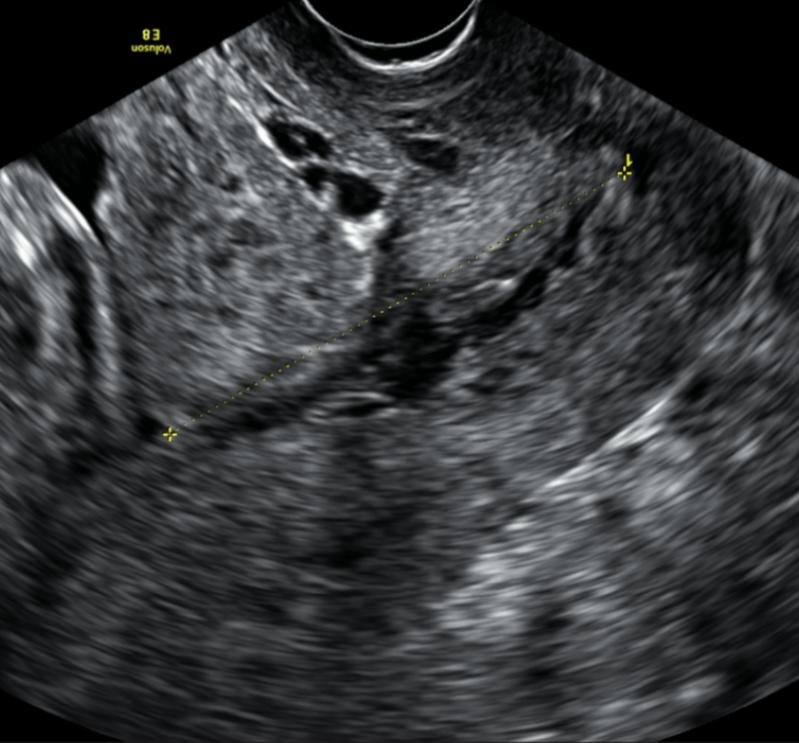

3. Underdeveloped lower uterine segment

At early gestations, less than 20 weeks, the lower uterine segment is not always fully developed and can mimic a long cervix. It is important therefore to make sure the internal os is correctly identified. Identifying the cervical glands and bladder angle as landmarks can help with this (Figure 1).

Figure 1. Example of an underdeveloped lower uterine segment, red arrows indicate underdeveloped lower uterine segment.